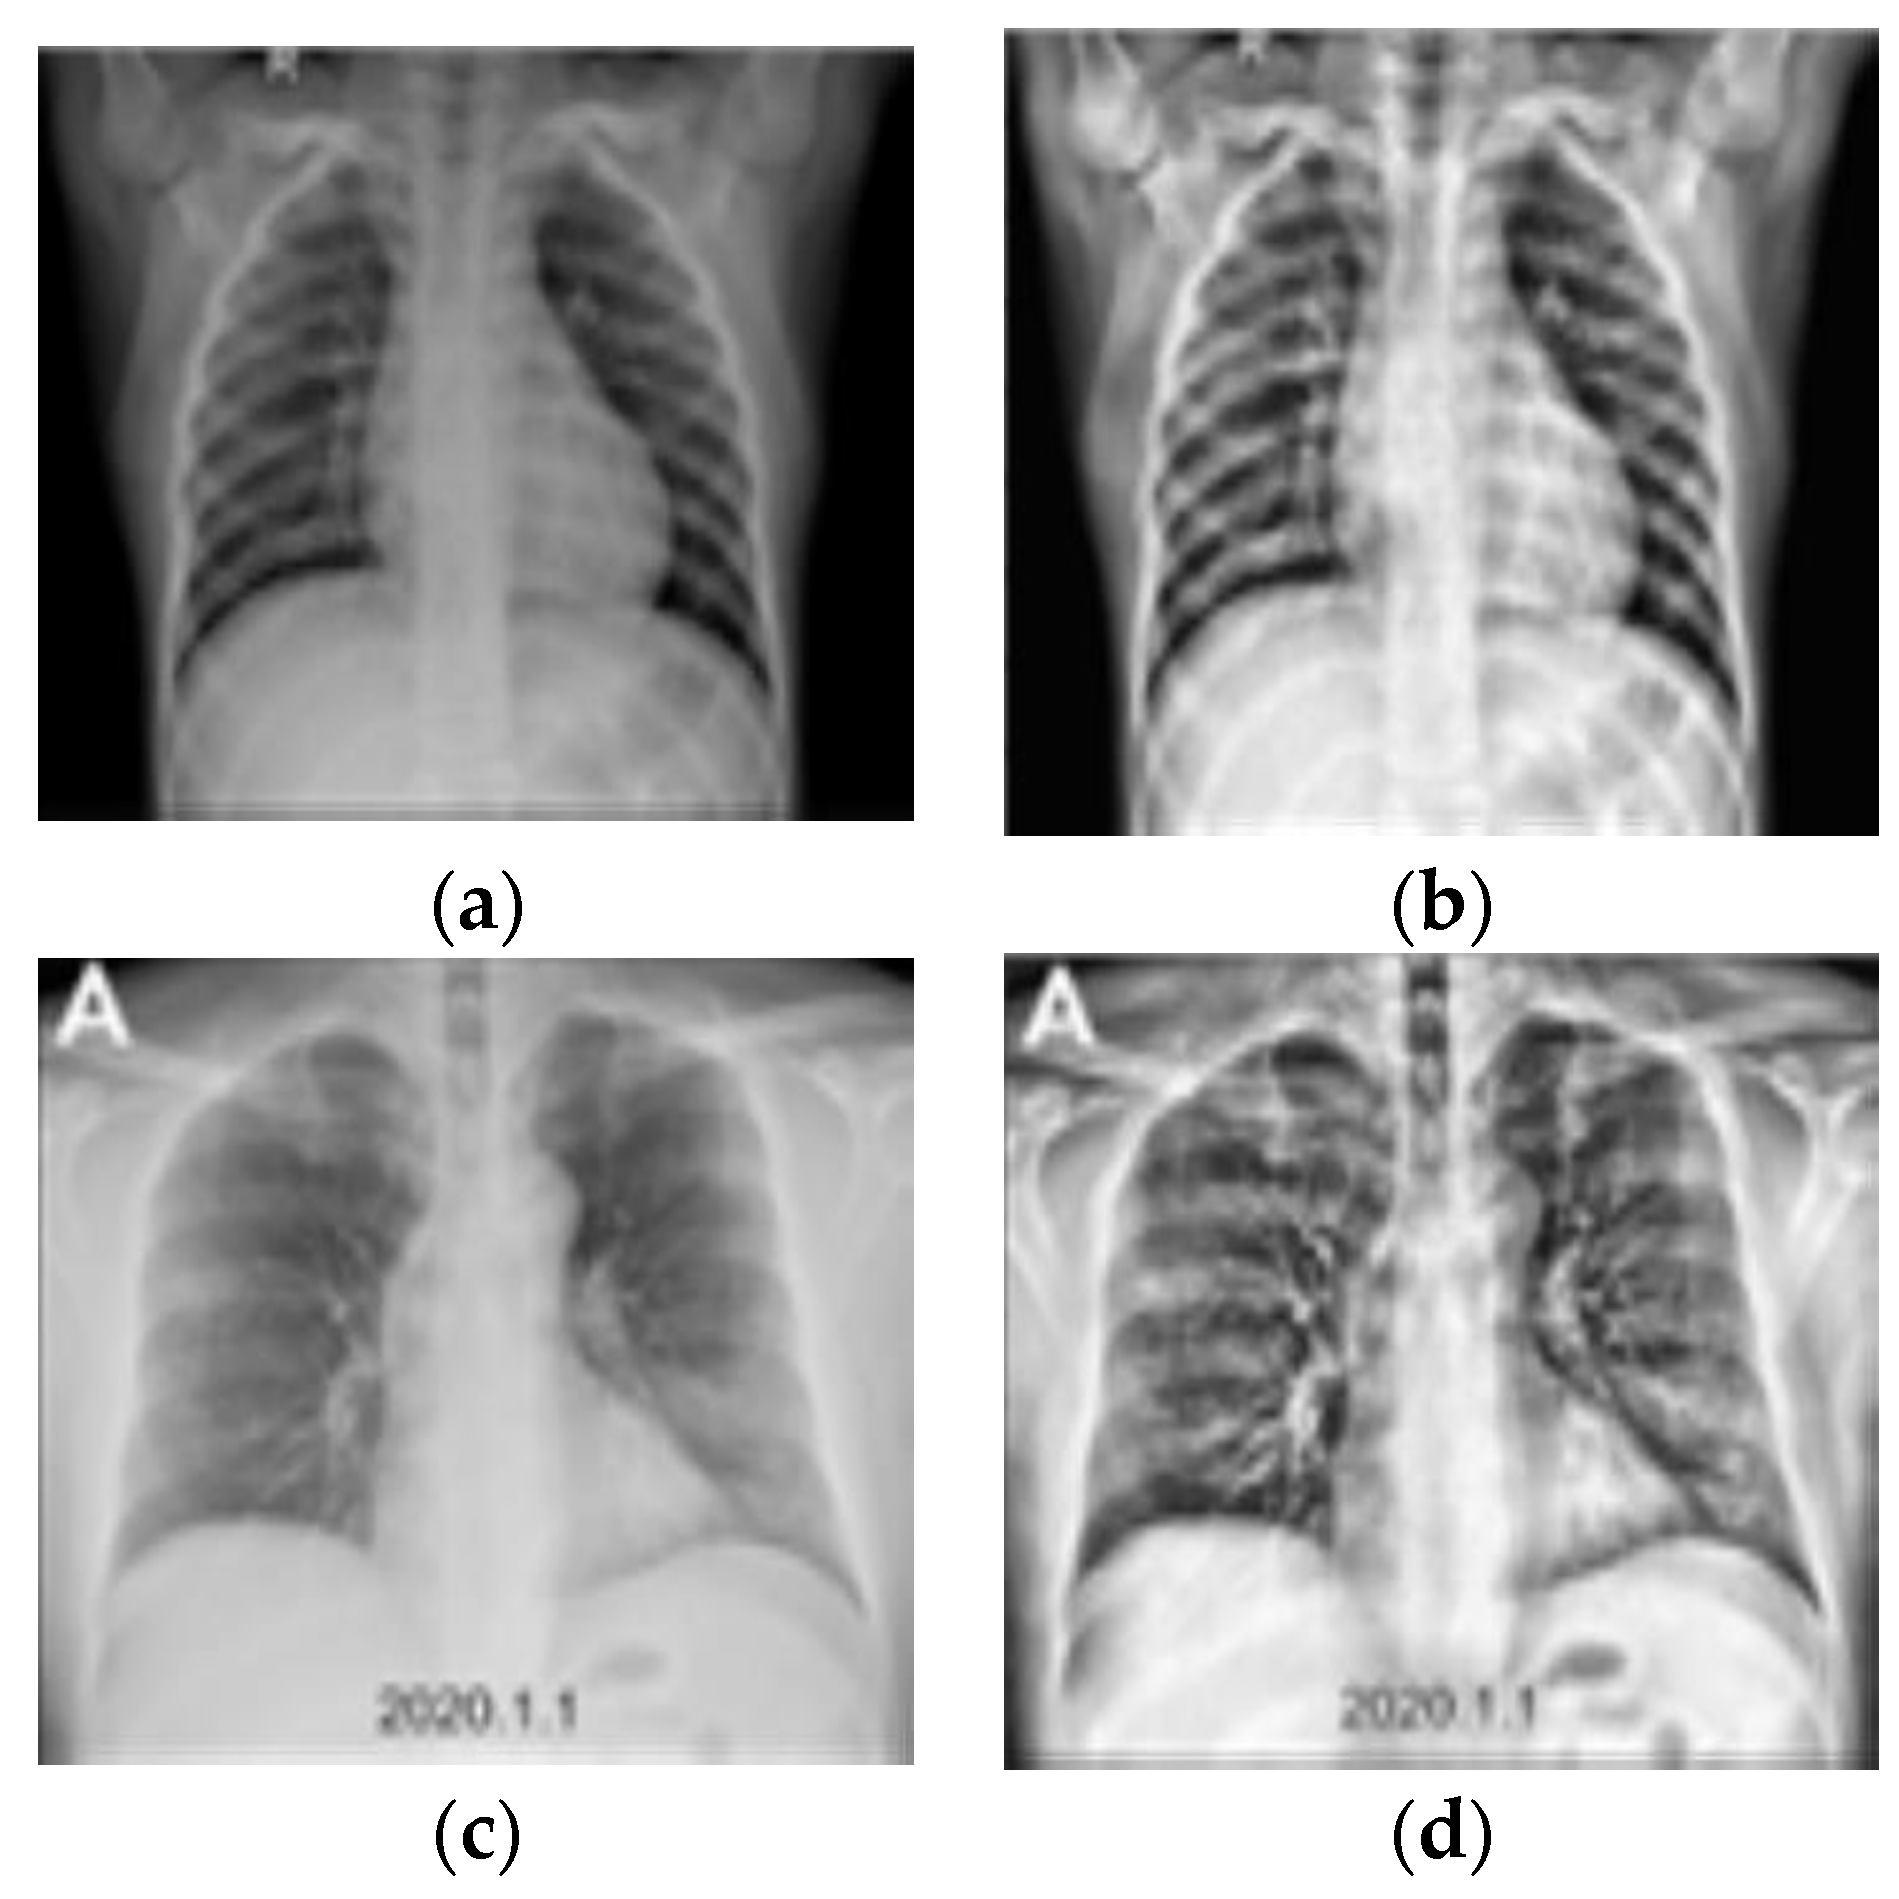

3.2. Preprocessing